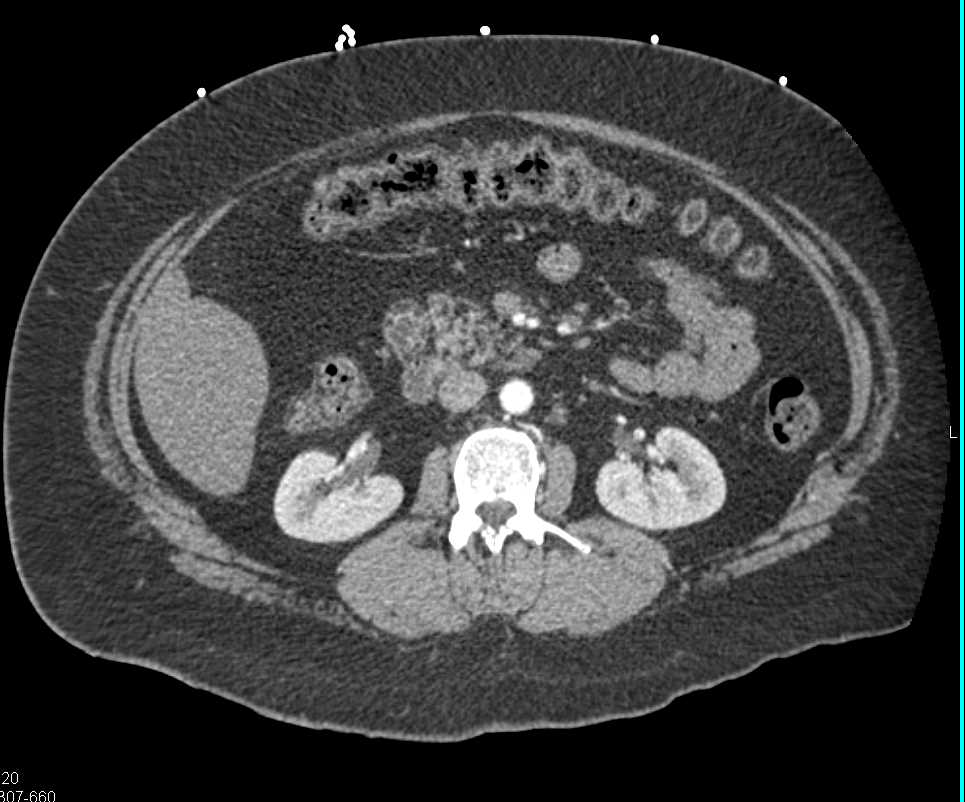

Infectious Enteritis Involving the Ileum